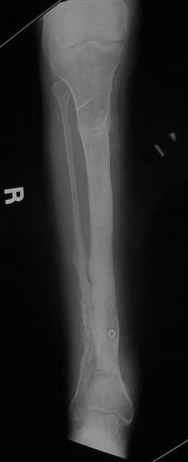

The case:Женщина 24 лет non union дистальной тибии с укорочением 7cm.

Все началось с перелома голени лет 8 тому назад. Остеомиелит - Илизаров в Kentucky, USA (деталей нет) и полтора года тому назад перелом средней трети тибии (1). Наложен унилатеральний фиксатор. Перелом зажил, но образовался стержневой остеомиелит дистального стержня. Потом нон юнион. В настоящий момент нет клинических признаков инфекции. Раны зажили.(2) Нон юнион подвижный и есть незначительное движение в голеностопе. Укорочение 7см. (3) Хотел бы знать мнение участников Форума. Благодарю. Nikolaj Wolfson,West Virginia, USA

LNS> юнион подвижный и есть незначительное движение в голеностопе. Укорочение

LNS> 7см. (3)

По представленным снимкам мне не удалось понять форму и рзмеры отломков. по-моему, нет чистой боковой проекции. Интересно бы поглядеть на более информативные снимки.